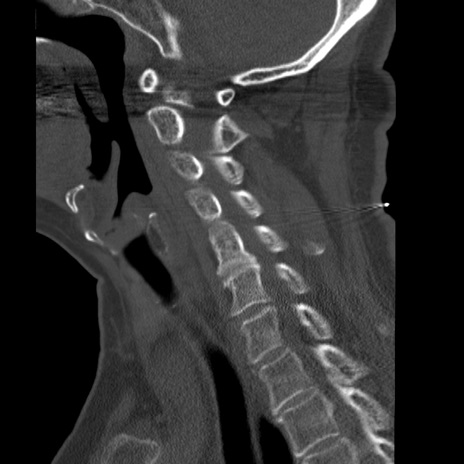

症例50 頚椎CT(矢状断像)

【症例】60歳代女性

【主訴】後頭部〜右後頸部にかけての痛み

【現病歴】本日飲食店でコーヒーを飲んでいたところ、突然後頭部〜右後頸部にかけて痛みが出現し、右上肢の感覚障害を伴ったため救急要請。

【身体所見】脳神経学的に明らかな異常所見を認めず。右上肢に軽度の感覚障害あり。

異常所見と診断は?

頚椎CT